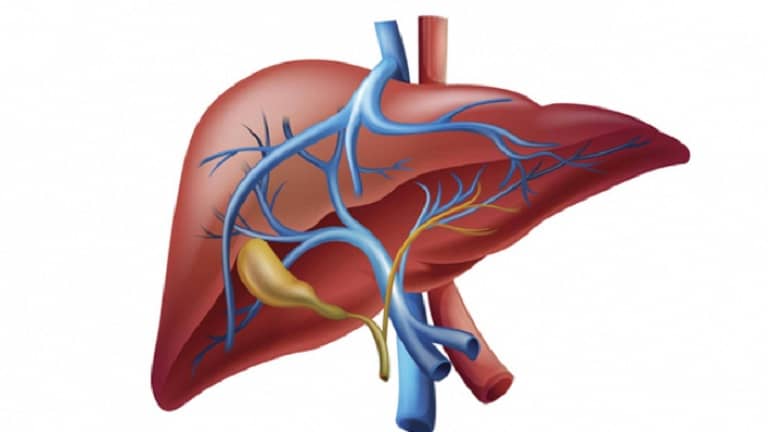

Hỗ trợ điều trị viêm gan:

Đây là một trong những công dụng được quan tâm nhiều nhất của cây chó đẻ. Năm 1982, Break Stone đã gây được sự chú ý đối với toàn thế giới về tác dụng chống virus viêm gan B của cây thuốc này. Những thử nghiệm lâm sàng trên trẻ em với bệnh viêm gan truyền nhiễm bằng một chế phẩm có Phyllanthus amarus của Ấn Độ đã cho kết quả nhiều hứa hẹn.

Sau 30 ngày uống cây chó đẻ (900mg/ngày) 50% những yếu tố lây truyền trong máu của virus viêm gan B (sinh kháng thể bề mặt của viêm gan B) đã mất đi. Bột Diệp hạ châu (Phyllanthus niruri) cho kết quả tốt với bệnh nhân viêm gan B khi uống 900 – 2.700mg trong 3 tháng liên tục.

Nghiên cứu của Nhật Bản và Ấn Độ trong năm 1980 đã xác định những tác dụng điều trị bệnh gan của cây chó đẻ là do phyllanthin, hypophyllathin và triacontanal.

Tại Việt Nam, khá nhiều công trình nghiên cứu về tác dụng điều trị viêm gan của cây chó đẻ đã được tiến hành, chẳng hạn: nhóm nghiên cứu của Lê Võ Định Tường (Học Viện Quân Y – 1990 – 1996) đã thành công với chế phẩm Hepamarin từ Phyllanthus amarus; nhóm nghiên cứu của Trần Danh Việt, Nguyễn Thượng Dong (Viện Dược Liệu) với bột Phyllanthin (2001).

Không được dùng nếu không mắc bệnh về gan mật

Đối với những người mắc các bệnh về gan hoặc mật thì việc sử dụng Cây chó đẻ răng cưa hỗ trợ điều trị sẽ rất tốt. Tuy nhiên đây là loại cây chữa bệnh, không nên uống hàng ngày để phòng bệnh, vì với người bình thường rất dễ gây tổn thương, mất cân bằng chức năng gan, mật,.. từ đó rất dễ dẫn đến chai gan, xơ gan.

Đây là loại cây chữa bệnh, không có tác dụng làm thuốc bổ vì vậy bạn không được tự ý sắc nước uống hằng ngày. Việc lạm dụng có nguy cơ làm phá vỡ hồng huyết cầu, từ đấy làm suy giảm hệ miễn dịch, hư hại chức năng gan.